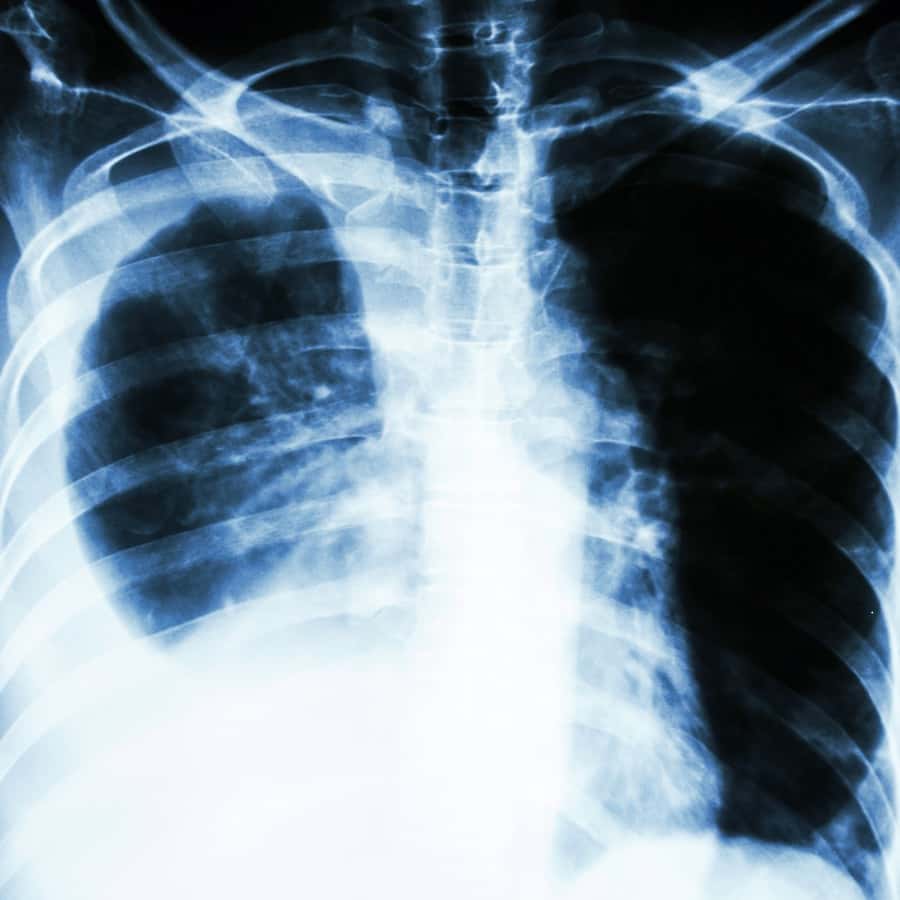

Six years ago, oncologists reported that patients with hard-to-treat lung cancer got significant benefit from nivolumab treatment (World Conference on Lung Cancer, Barcelona, Sep. 10, 2019). The study included 854 people. These individuals had non-small-cell lung cancer that had failed to respond to first-line platinum chemotherapy.

Since that time, oncologists have begun using nivolumab (Opdivo) and the related pembrolizumab (Keytruda) to treat many patients with non-small-cell lung cancer. The drugs can be a real boon, but not everyone responds to them as we would wish. Now researchers report a relatively simple hack can nearly double a patient’s chance of survival.

Researchers reported that patients with non-small-cell lung cancer who got an mRNA COVID vaccination when they started treatment with nivolumab were almost twice as likely to survive three years than those who remained unvaccinated. The results were presented at the meeting of the European Society for Medical Oncology. The scientists found that 55 percent of those who were vaccinated were still alive three years later, compared to 30 percent of those who did not get the vaccine. They suspect that the vaccine alerts the immune system, waking it up in a sense, and sensitizes the tumor to the PD-1 inhibitor.